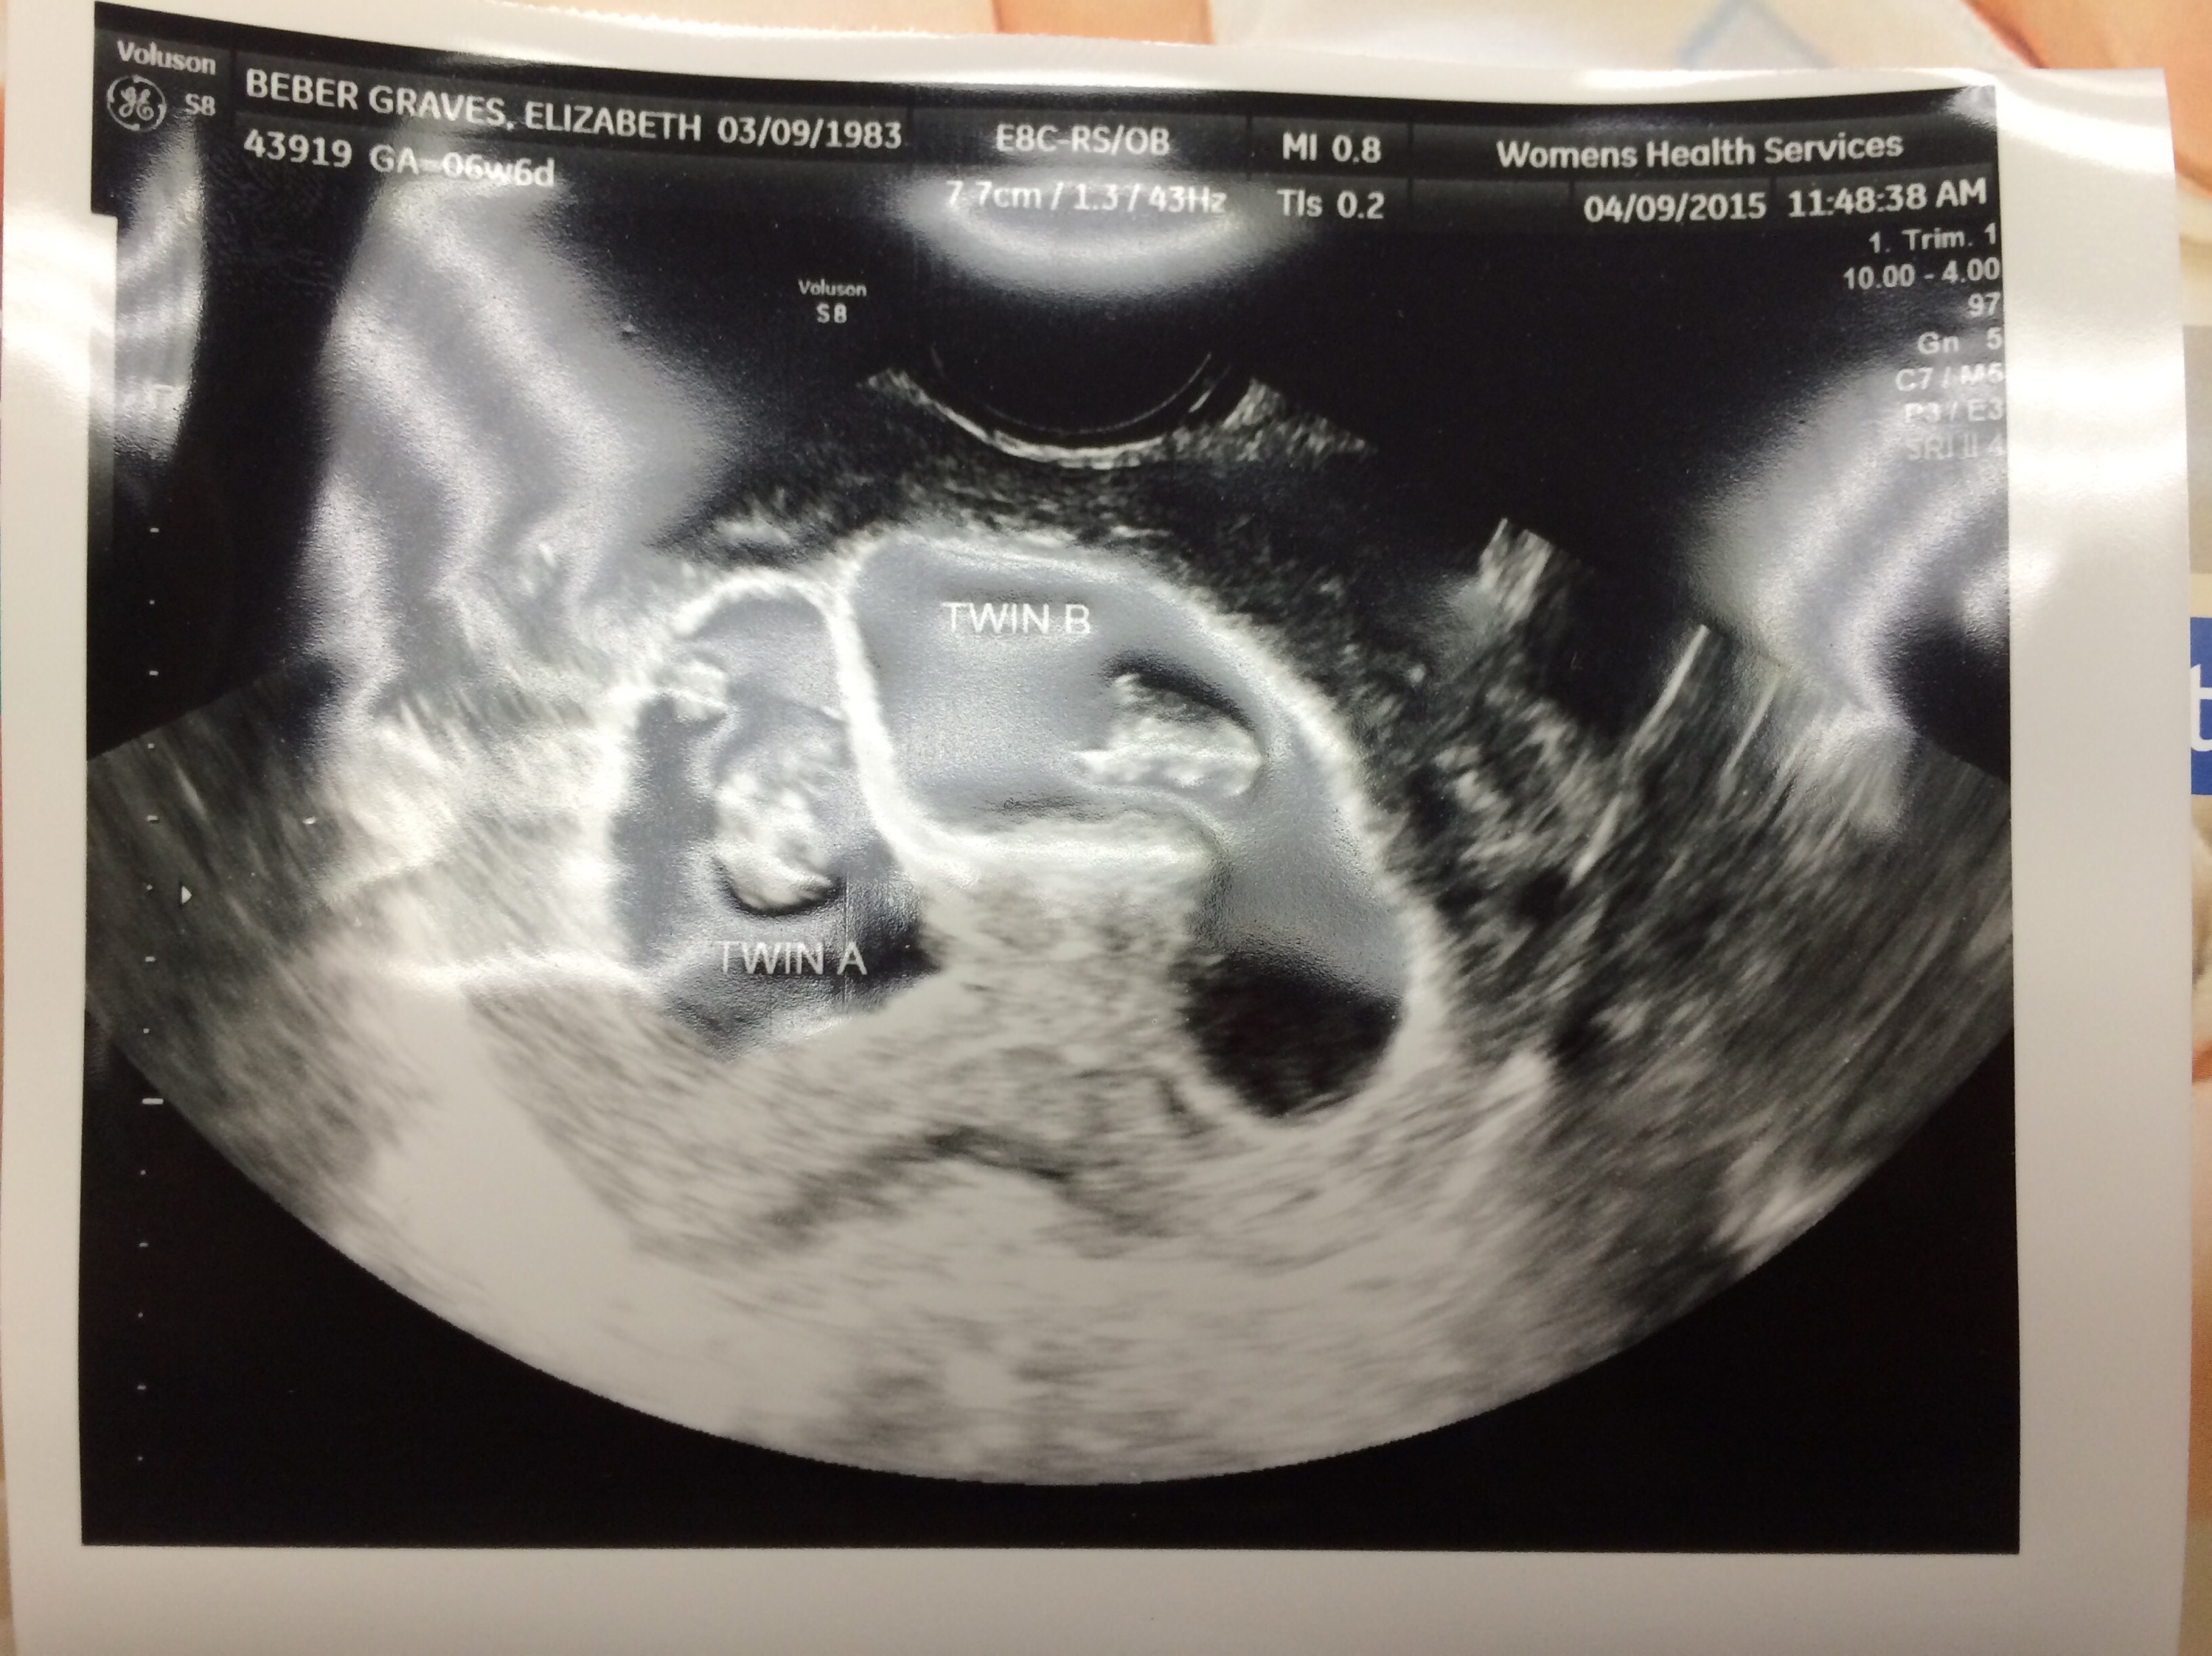

So when we went in for our first ultrasound, I was very nervous. Garen kept reassuring me that it would be fine. As I lay there during the ultrasound, the doctor took a very long time probing before saying anything. So long that I got nervous something had happened to the baby. Instead, a moment later she asked, “How do you feel about twins?” And she showed us this….

Time stood still. I asked if she was joking and, in a deadpan tone, she asked “Why would I joke about something like this?” That made it worse. I started to cry. My fear had come true and my mental plan to “prepare myself” completely failed. I’m not sure anything could have prepared me for that.